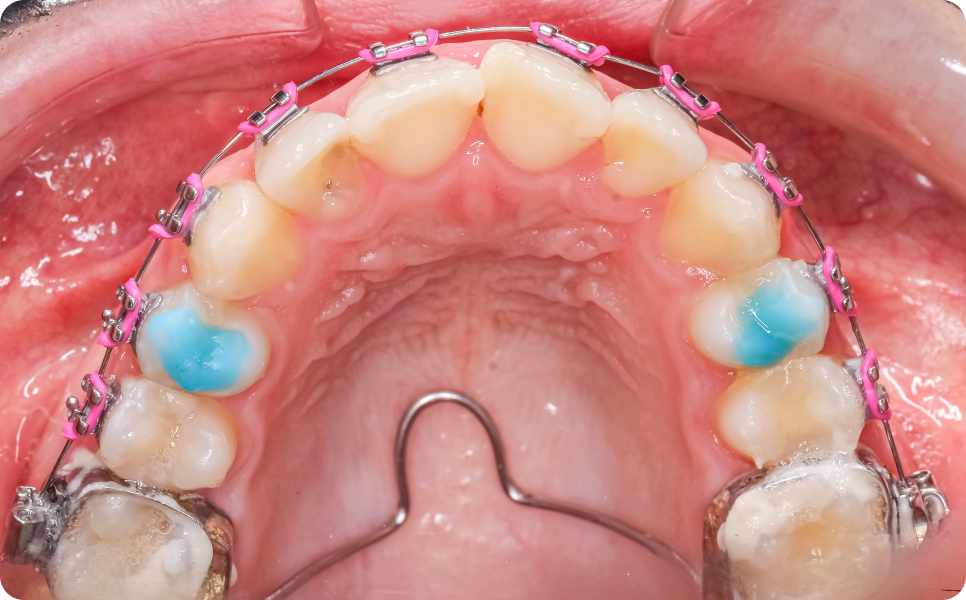

Le Quad Hélix est constitué d’un fil métallique formé de plusieurs boucles (« hélix »), fixé sur les molaires supérieures à l’aide de bagues.

Une fois en place, l’appareil exerce une pression douce et continue sur les dents et l’os.

Le Quad Hélix est posé au cabinet lors d’un rendez-vous dédié. La pose est indolore. Une sensation de pression ou de gêne peut apparaître dans les jours suivants, le temps que la bouche s’habitue. - Phase d’expansion